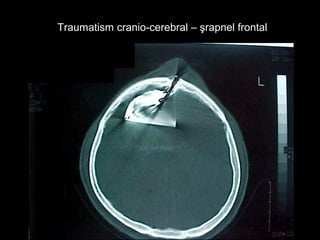

Traumatism cranio-cerebral – şrapnel frontalTraumatism cranio-cerebral – şrapnel frontal

Traumatism cranio-cerebral –şrapnel frontalTraumatism cranio-cerebral – şrapnel frontal